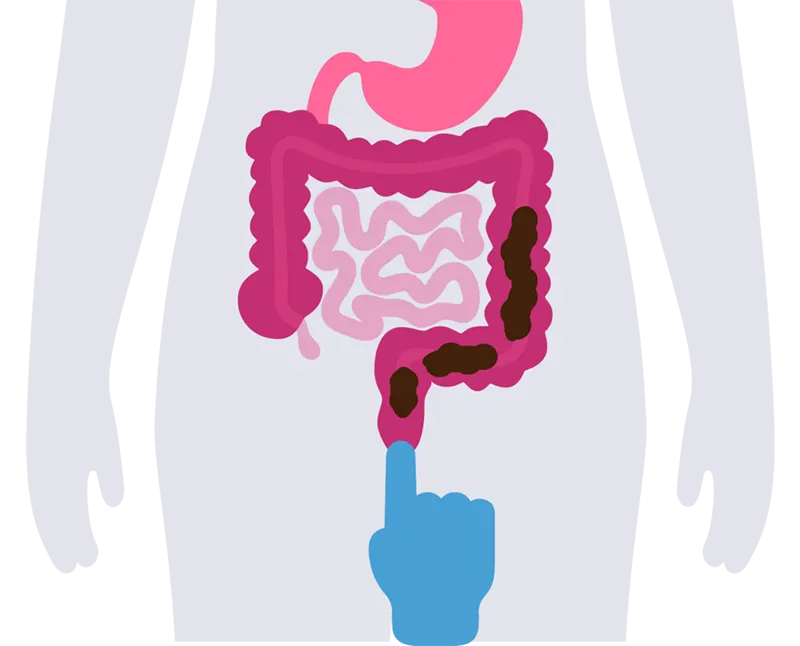

رفلاکس مدفوع (بازگشت مدفوع به روده) یک اختلال نادر و پیچیده گوارشی است که در آن مواد دفعی پس از ورود به راست روده در حین اجابت مزاج، مجدداً به داخل روده بزرگ بازمی گردد. این وضعیت به دلایل مختلفی از جمله اختلال در حرکات پریستالتیک روده و عدم عملکرد درست اسفنکترهای مقعد رخ می دهد. برخلاف رفلاکس معده که نسبتاً شایع و شناخته شده است، رفلاکس مدفوع خیلی شناخت شده نیست.

در یبوست های شدید که مدفوع سفت شده و نمی تواند به راحتی از بدن دفع شود نیز ممکن است رفلاکس مدفوع رخ دهد. یبوست باعث تجمع مدفوع در ناحیه انتهایی روده و بازگشت بخشی از آن به داخل روده خواهد شد.

انسداد روده یکی دیگر از علل بازگشت مدفوع به روده است. انسداد روده می تواند ناشی از وجود تومورها، چسبندگی ها (به ویژه پس از جراحی های شکمی)، یا تنگی مادرزادی یا اکتسابی باشد که در خروج مدفوع از بدن اختلال ایجاد می کند.

رفلاکس مکرر و عدم تخلیه نامناسب مدفوع همچنین ممکن است باعث انسداد جزئی یا کامل روده شود که نیاز به درمان فوری دارد. عفونت های گوارشی به دلیل رشد باکتریهای ناسالم در روده یکی دیگر از عوارضی است که در رفلاکس مدفوع اتفاق می افتد.